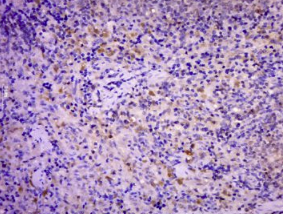

多聚甲醛固定,石蜡包埋(大鼠脾脏);经柠檬酸钠缓冲液(pH6.0)煮沸15min后获得抗原;用3%过氧化氢阻断内源过氧化物酶20分钟;阻断缓冲液(正常山羊血清)在37℃下30min;用(phospho Bim(Ser77))进行抗体孵育。未结合的多克隆抗体在1:500下在4°C下过夜,然后结合二级20分钟,DAB染色。